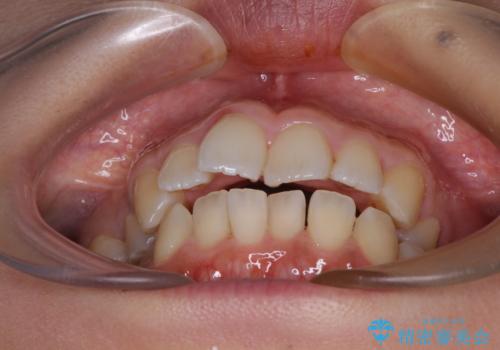

前歯のデコボコを改善 インビザラインの矯正治療

- 前歯のデコボコを治したいとのことで来院された患者様です。

上下顎ともに歯列全体の後方移動とIPR(歯と歯の間を削る)によってデコボコが解消するように設計し、インビザラインにより治療を行うこととしました。

下顎前歯は後戻りを起こしやすいため、舌側を細いワイヤーで固定し、マウスピース型リテーナーで保定を行うこととしました。